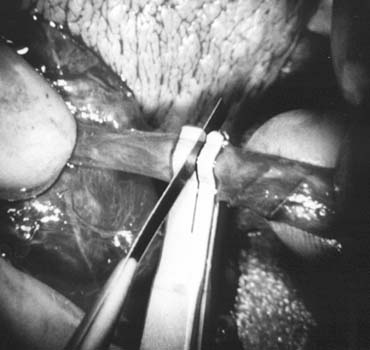

Microsurgical End-to-Side Intussusception Technique

This method, also known as the triangulation technique,43 has gained increasing popularity among microsurgeons over the conventional end-to-end and end-to-side vasoepididymostomy.4,44,45,46 When the level of epididymal obstruction is clearly demarcated by the presence of markedly dilated tubules proximally and collapsed tubules distally, the site at which the anastomosis should be performed is readily apparent (Figs. 19 and 20). The vas deferens is drawn through an opening in the tunica vaginalis and secured in proximity to the potential anastomotic site in the epididymis with two to four interrupted sutures of 6-0 polypropylene placed through the vasal adventitia and the epididymal tunica (Fig. 21). Six microdots are placed on the cut surface of the vas in an identical fashion to that described for vaso-vasostomy (Fig. 22). Three 10-0 double-armed nylon sutures are placed in the epididymal tubule in a triangular fashion (Fig. 23). The needles are not pulled through but left in situ, creating a triangle of needles. A generous opening is made in the epididymal tubule in the center of the triangle created by the three needles. The three needles are then pulled through (Fig. 24). A glass slide is touched to the fluid exuding from the opening in the epididymal tubule and mixed with human tubal fluid media, covered with a cover slip and examined by the surgeon using the separate bench microscope under 400-power magnification. If sperm are present (whether motile or not) the decision is made to proceed with the anastomosis. Sperm are aspirated into micropipettes first (Fig. 25) and expressed into human tubal fluid media and sent for cryopreservation if motility is observed. After abundant sperm have been aspirated into micropipettes and cryopreserved, the six needles are passed inside out the vas deferens exiting through the six previously placed microdots in the order indicated (Fig. 26). Each pair of sutures is then sequentially tied. Tying of these sutures intussuscepts the epididymal tubule into the vas lumen (Fig. 27). This creates a water-tight closure. In addition, the flow of epididymal fluid from the epididymal tubule into the vas deferens tends to plaster the edges of the epididymal tubule against the mucosal walls of the vas deferens, further helping create a leakproof closure. The second layer of the anastomosis is completed using interrupted 9-0 nylon sutures to secure the epididymal tunica to the vasal sheath (Fig. 28).

Fig. 19. Inspection of the epididymis for dilated tubules (arrow) seen beneath the epididymal tunica.

Fig. 20. Dissection exposing dilated loops of epididymal tubule (arrow).